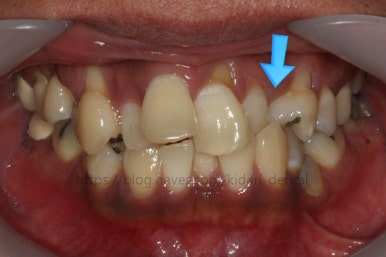

화살표 부분에 원래 송곳니가 있어야 되는데 보이질 않네요. 결손치아일 수도 있고 매복치아일 수도 있겠어요.

왼쪽 위 어금니도 한 개가 없어서 빈공간이 약간 남아있어요.

왼쪽 아래 작은 어금니는 아래쪽으로 많이 꺼져있네요.

이런 경우 X-ray 도 면밀히 관찰해 줘야 합니다.